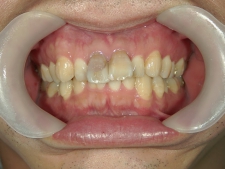

矯正歯科 治療後 E-AMXというセラミックにて左右上1番を被せ直しました。

no.24_8228_治療後_右.jpgno.24_8228_治療後_正面.jpgno.24_8228_治療後_左.jpg